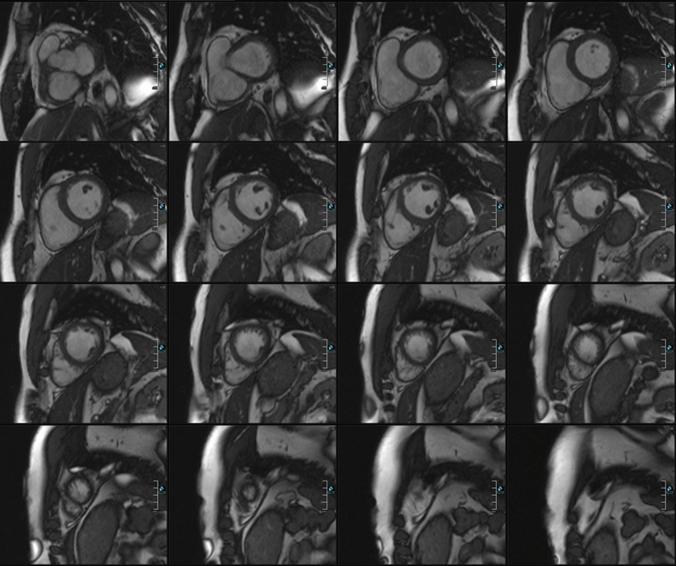

The obstructive sleep apnoea syndrome (OSAS) is a disorder with a high prevalence and is associated with an elevated cardiovascular risk and increased morbidity and mortality. For longitudinal studies and functional analysis cardiac MRI is regarded as the gold standard. Aim of this study was to evaluate the long-term effect of continuous positive airway pressure (CPAP) therapy on cardiac functional parameters with cardiac Magnetic Resonance Imaging (cMRI). 54 patients with OSAS (mean apnea hypopnea index-AHI: 31) were prospectively enrolled in this study and cMRI was performed before and after 7 months of CPAP therapy. Data were acquired on a 1.5 T MRI and right and left ventricular cardiac function were analysed. CPAP treatment was considered compliant when used ≥ 4 h per night. 24-h blood pressure was measured at baseline and follow up. 33 patients could be assigned to the compliance group. Left ventricular stroke volume (LV SV) and right ventricular ejection fraction (RV EF) improved significantly with CPAP therapy (LV SV from 93 ± 19 to 99 ± 20 ml, p = 0.02; RV EF from 50 ± 6 to 52 ± 6%, p = 0.04). All other cardiac parameters did not change significantly while mean systolic and diastolic blood pressure improved significantly (p < 0.01). 21 patients were assigned to the non-compliance group and were considered as a control group. There were no relevant differences in cardiac parameters between baseline and follow up examination in these patients. CPAP therapy seems to improve LV SV, RV EF, systolic and diastolic blood pressure in OSAS patients, but reproducibility of our results need to be confirmed in a larger patient population.